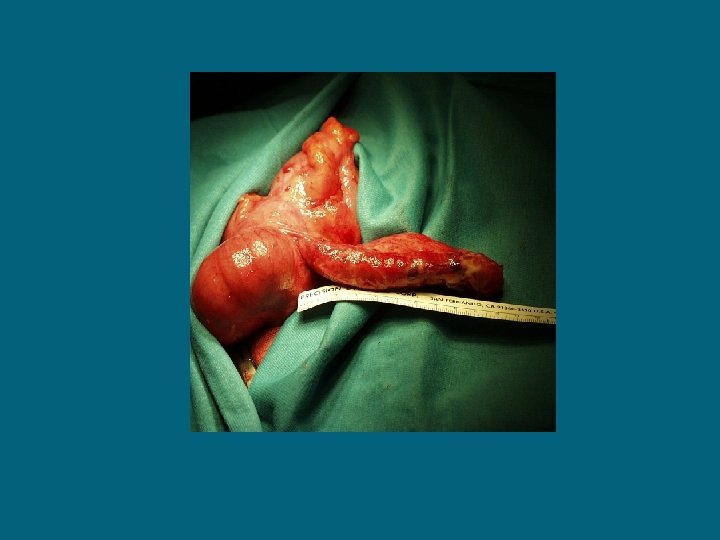

volvolo

Volvolo su briglia aderenziale

Invaginazione intestinale